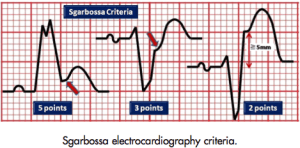

Bei den Sgarbossakriteren sind die ST-Segmente konkordant (Sgarbossa A und B) (Abbildung 2) bzw. extrem diskordant (C bzw. modifiziert nach Smith).

Abb. 2: Sgarbossa Kriterien A, B und C, Konkordante Hebungen bei LSB (Sgarbossa A links, 5 Punkte und Sgarbossa B: Mitte, 3 Punkte) Exzessive ST-Diskordanz bei Sgarbossa C (rechts, besser ist allerdings die modifzierte Version nach Smith)

Definitionen:

- Sgarbossa A: konkordante ST-Segment Elevation > 1 mm in zumindest einer Ableitung (5 Punkte)

oder

- Sgarbossa B: konkordante ST-Segment Depression von mindestens 1 mm in Ableitung V1, V2 oder V3 (3 Punkte) oder

- Sgarbossa C: ST Elevation ≥5 mm in einer Ableitung mit negativem (diskordantem) QRS Komplex. (2 Punkte)

Dies ergibt bei ≥ 3 Punkten eine Sensitivität von 78% und eine Spezifität von 90%.